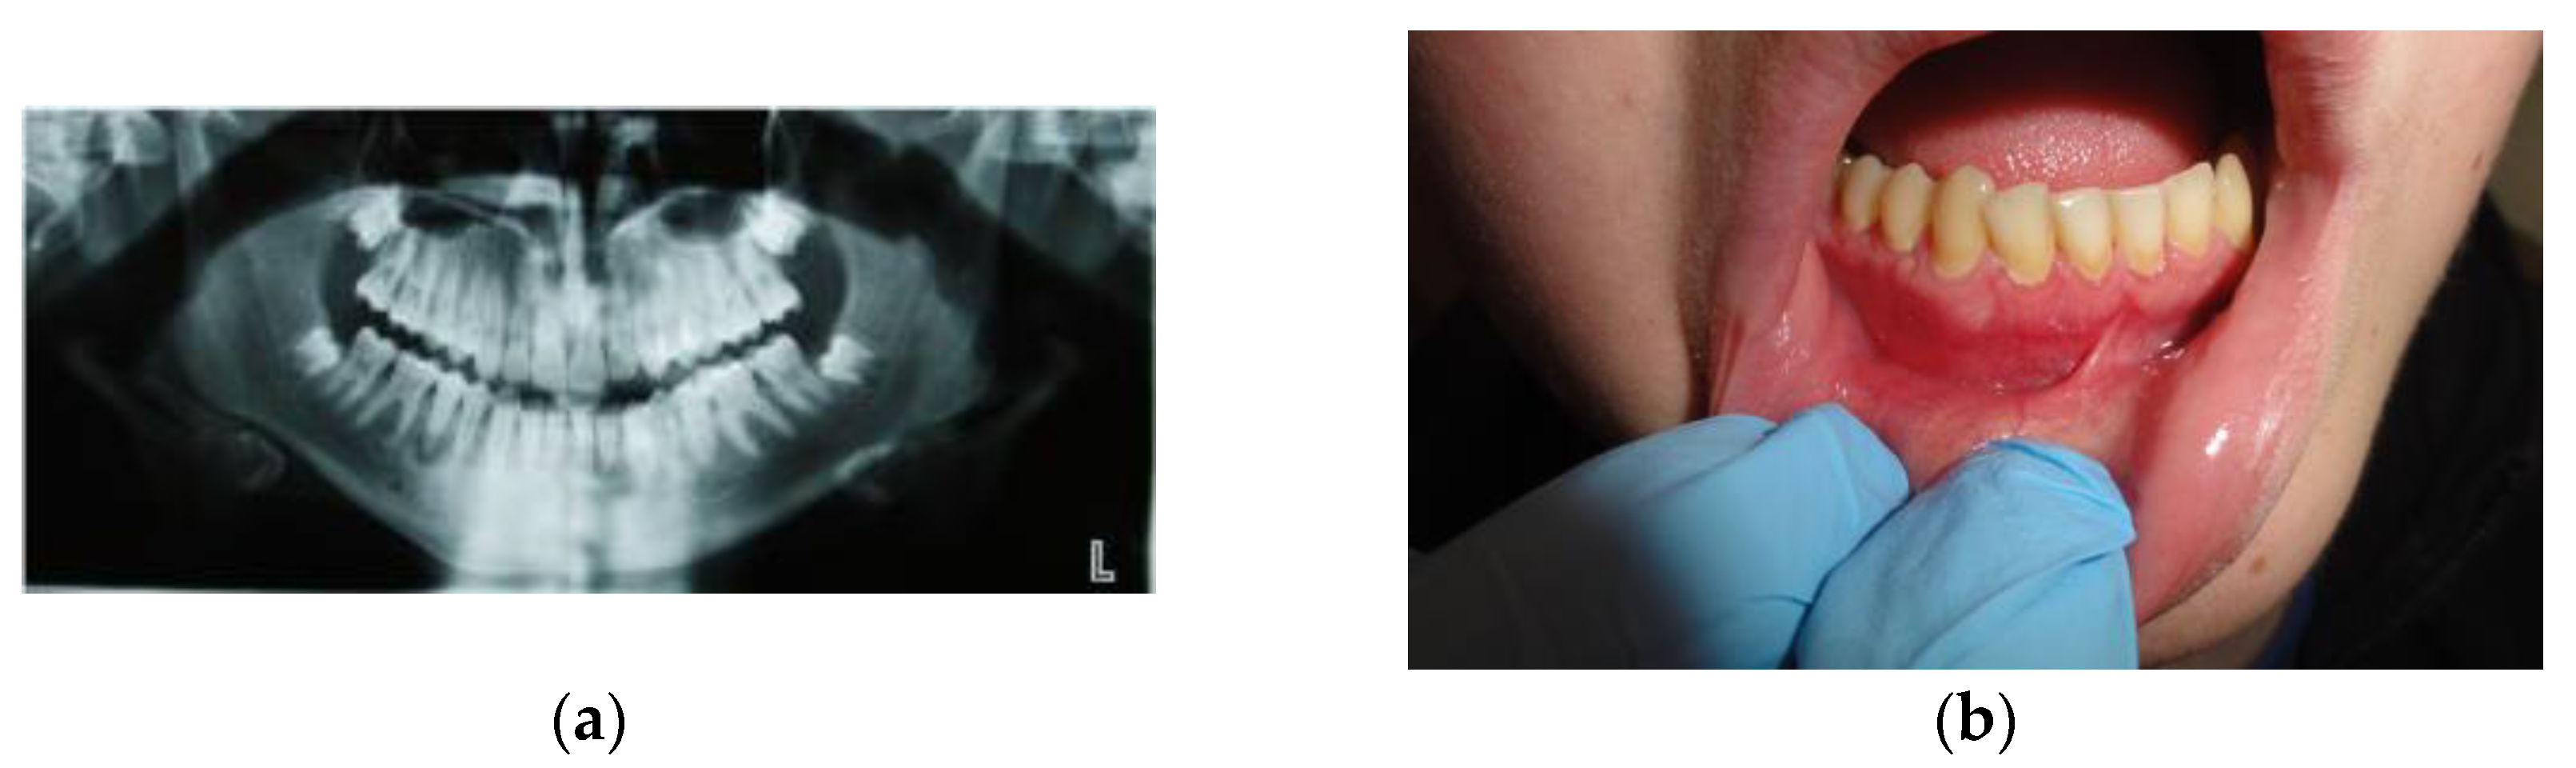

2.1. Case #1

| Case #1 | 14 y.o. | Male | Dexamethasone for 3 months 12 mg/3 mL every week and then 8 mg/12 mL every 2 weeks for the next 3 months | Mandible | Yes | Success | 9 years |